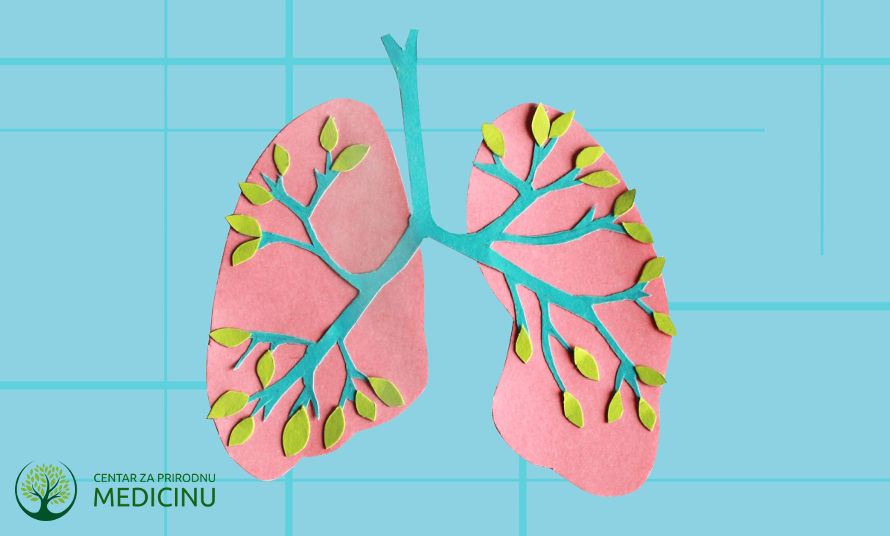

Anatomija pluća

Vašem telu je neophodan kiseonik, koji dobijete iz vazduha koji udišete.

Emfizem je postao najčešća infekcija pluća savremenog zapadnog sveta. Da bismo preživeli, mi svakoga dana iskoristimo oko 30 kubnih metara vazduha. On prolazi kroz površinu naših pluća, koja ako bi se prostrla da budu ravna, bila bi veličine jednog teniskog terena. Kod emfizema velik broj alveola (kesice koje liče na grozd i u kojima se vrši razmena gasova) je uništen i krv ne dobija dovoljno kiseonika.